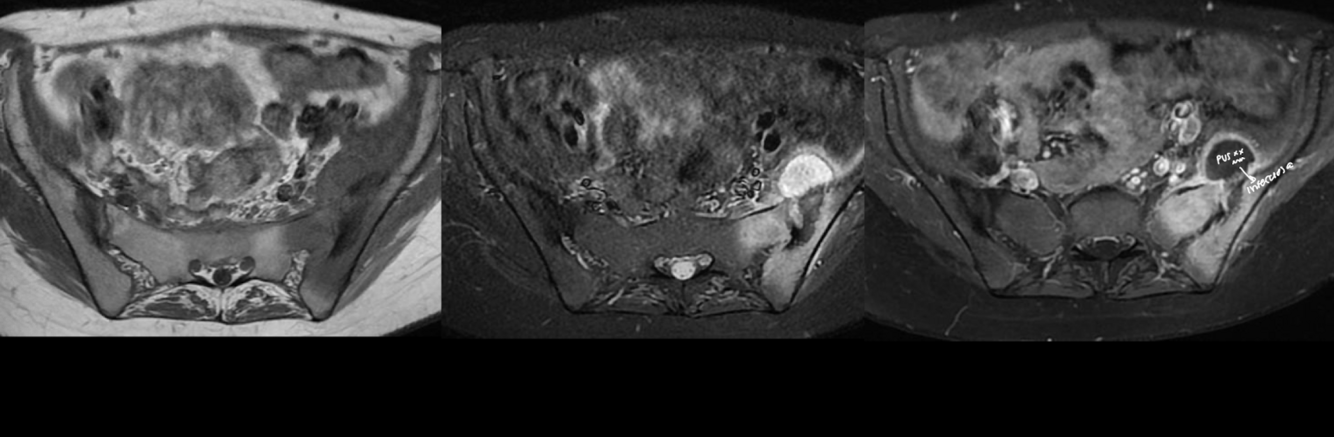

RM

A

LO MEJOR

lx pequeñas

episodioa agudo

involucro otras estructuras

Hiper T2, fat sat, STIR

Hipo T1

CAPTACIÓN CONTRASTe